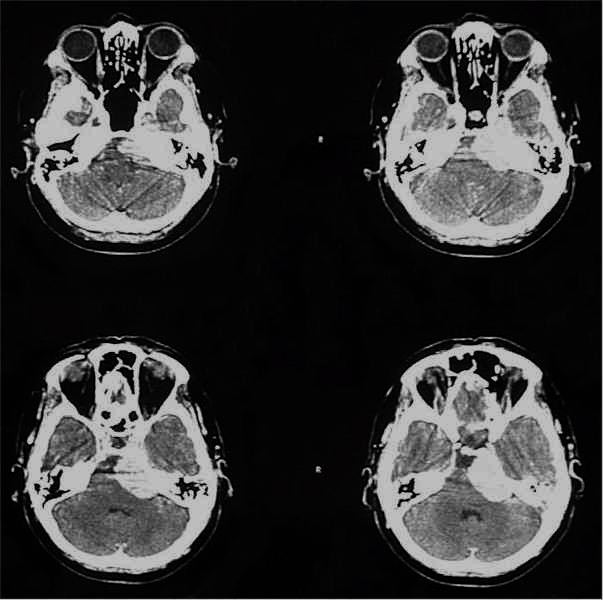

TC preoperatoria

TC postoperatoria

RM preoperatoria

RM postoperatoria